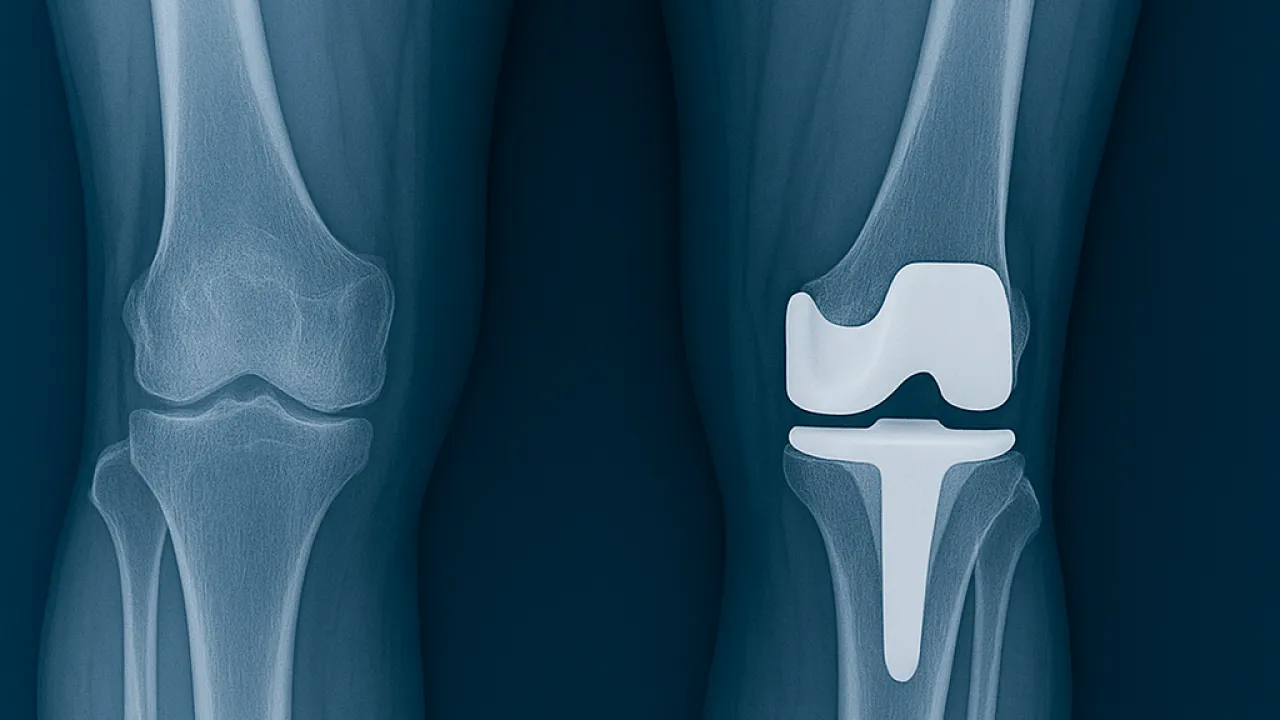

Eklem protez cerrahisi (artroplasti), halk arasında “eklem protezi” olarak bilinir. En çok kireçlenen eklem ve en çok protez uygulanan eklem diz eklemidir. Bunun ardından Kalça eklemi gelir. Ayrıca omuz, ayak bileği ve el bileği eklemlerinde de kireçlenme yani artroz sonrası eklem protez cerrahisi uygulanmaktadır. Eklemlerimiz zamanla yıpranabilir veya kireçlenme nedeniyle görevini yapamaz hale gelebilir. Bunun birçok sebebi vardır. Bu durumda protez cerrahisi sayesinde ağrısız hareket etmek, günlük hayata geri dönmek mümkündür. Türkiye'de protez cerrahisi 90'lı yıllarda İstanbul, İzmir ve Ankara gibi illerde yapılırken şu an her şehirde yapılabilmektedir. Ege Üniversitesi'nde diz protezi ve kalça protezleri konusunda 40 yıllık deneyimi olan Hakkı Sur ile eğitim aldıktan sonra Fransa'da yine ünlü protez merkezinde birçok vakaya katılmış ve yapmış olmanın bu cerrahideki önemini meslek hayatımda daha da idrak ettim.

En sık uygulanan eklem protezleri: